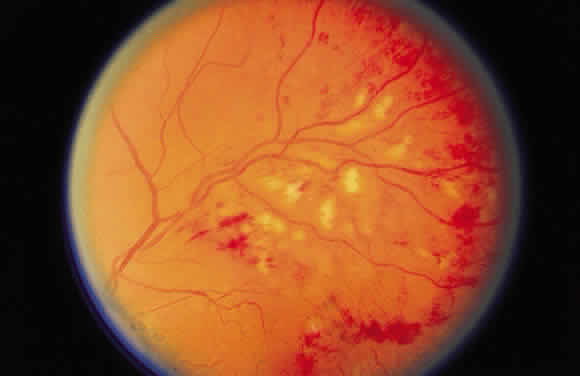

shape of the hemorrhage. Fresh hemorrhage on the retinal surface appears bright red, whereas fresh hemorrhage

beneath the retinal pigment epithelium seems much darker. A hemorrhage in the nerve fiber layer (Fig. 11A) dissects along the plane of the layer parallel to the orientation of

the internal limiting membrane (see Fig. 11B). A hemorrhage located between the retinal pigment epithelium and Bruch's

membrane also spreads in a plane parallel to the orientation

of the membrane (Fig. 12). However, its extent is limited by the adhesion of the pigment epithelium

to Bruch's membrane, in contrast to a nerve fiber layer hemorrhage, where

no such delineating structure is present. Therefore, a fresh

nerve fiber layer hemorrhage appears bright red and has feathery

borders, whereas a subpigment epithelial hemorrhage appears brown-black

and has sharp borders (Fig. 13).  Fig. 11. A. Section of retina with hemorrhage in the nerve fiber layer (between the two large arrows). Notice that the limits of the hemorrhage are not clearly defined, since

scattered red blood cells can be seen to the right of the right-hand

large arrow. This histologic picture corresponds to a clinically observed

fame-shaped hemorrhage with an indistinct border. The detached

posterior hyaloid is marked by four small arrows. B. Fundus photograph of nerve fiber layer hemorrhage. They are oriented parallel

to the plane of the internal limiting membrane. Because of their

dispersal within the ganglion cell layer, the borders are “feathery” (flame

shaped). Fig. 11. A. Section of retina with hemorrhage in the nerve fiber layer (between the two large arrows). Notice that the limits of the hemorrhage are not clearly defined, since